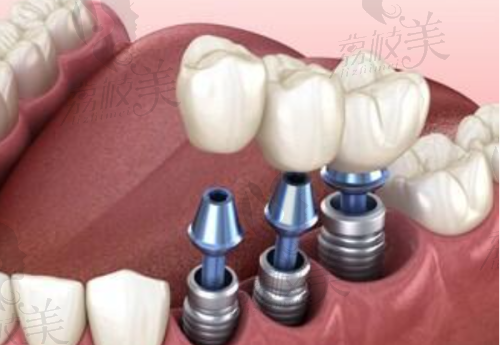

BioActive仿生设计模拟天然牙齿根部结构形态更贴合牙槽骨,长期稳固不松动

四重表面处理技术等离子喷砂 + 微孔腐蚀技术更容易跟牙骨融合,提升成功几率

短小体积适配狭窄牙槽小尺寸设计,较大限度保留原生牙结构骨量不足人群也可尝试种植